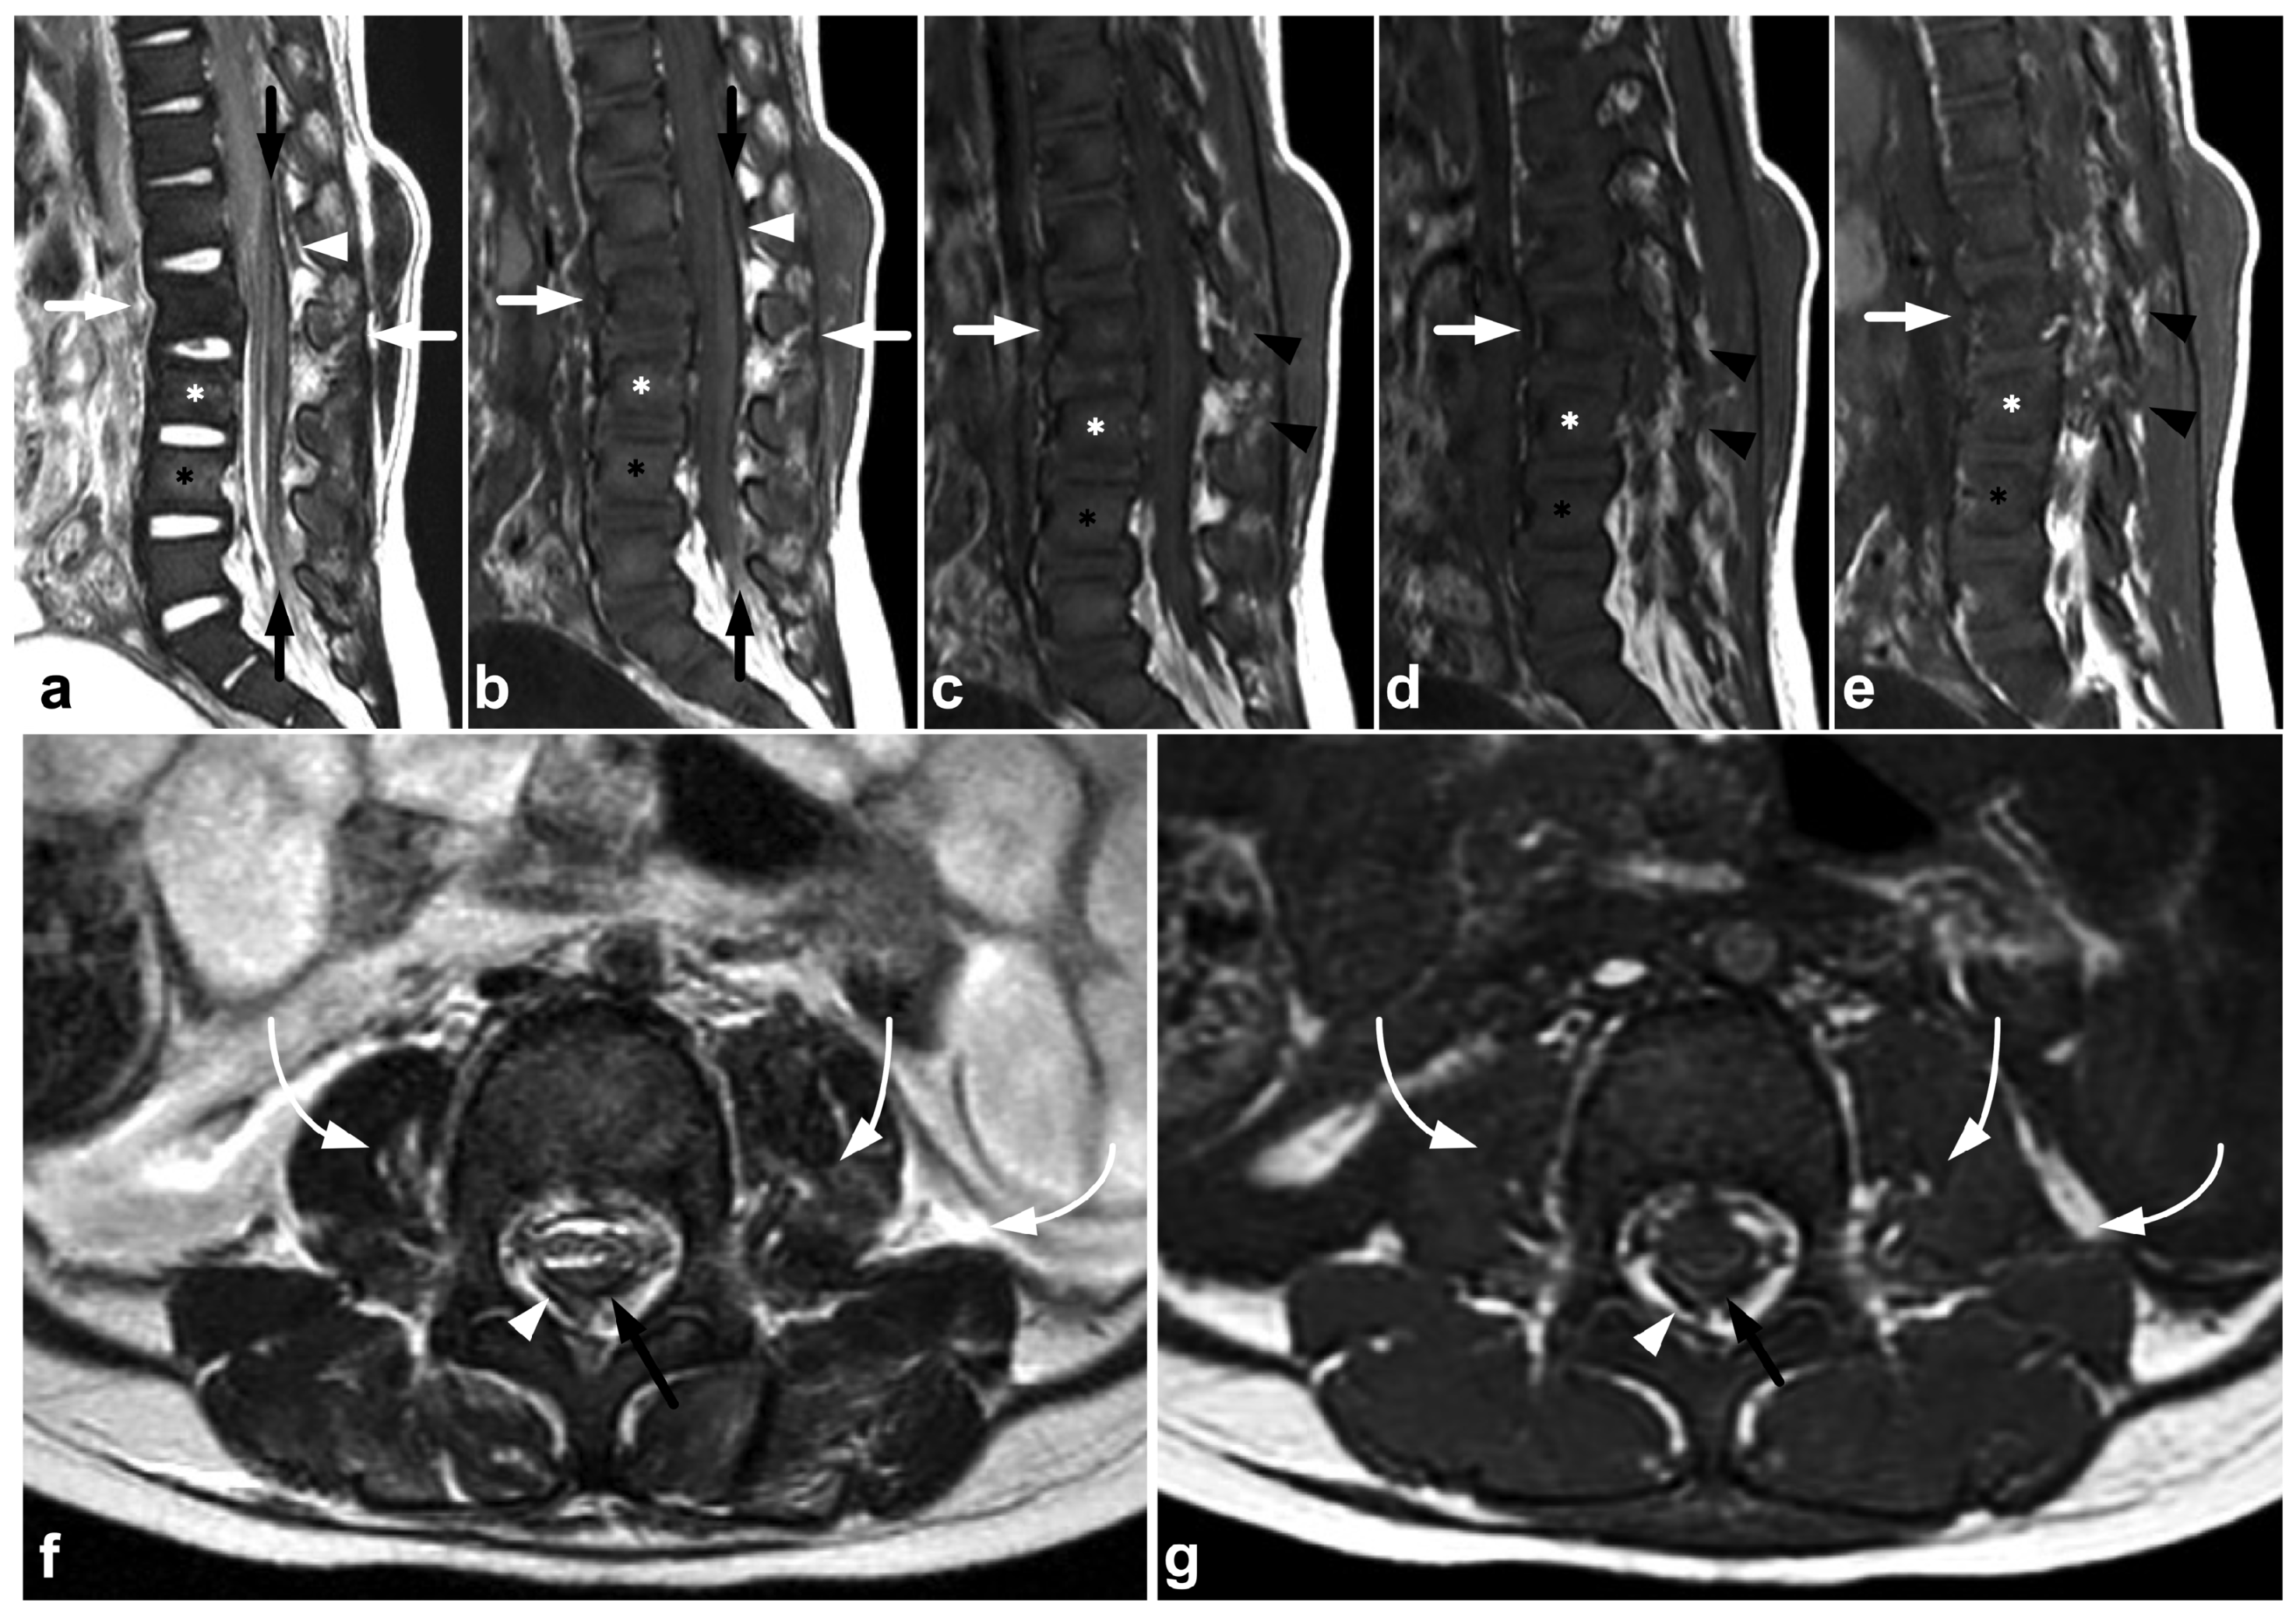

Figure 3.

(a) Sagittal T2-weighted. (b) Sagittal T1-weighted. (c) Sagittal left-sided off-midline T1-weighted. (d) Sagittal right-sided off-midline T1-weighted. (e) Sagittal left-sided off-midline T1-weighted. (f) Axial T2-weighted. (g) Axial T1-weighted. A 2-year-old female, motor vehicle accident. Chance-type fracture through the vertebral body and the posterior arch is seen in L2 (white arrows). L2/3 and L3/4 facet joints are widened and subluxated (black arrowheads). Kyphosis at level L2. Compression fracture in L3 (white asterisk) and contusion in L4 (black asterisk). Posteriorly, there is a longitudinal intradural hematoma (black arrows) and epidural hematoma (white arrowheads). A paraspinal hematoma (curved arrows) and posterior subcutaneous hematoma are also seen.